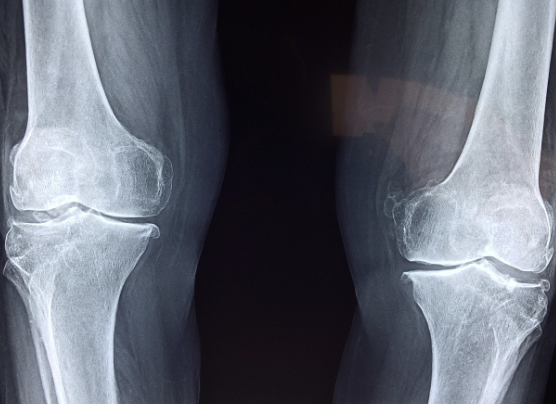

퇴행성 관절염 초기증상 (중년 이후 가장 흔한 타입)

나이가 들면서 연골이 닳아 발생하며, 50대 이후 여성에게 압도적으로 높습니다.

● 초기 특징

- 무릎 통증이 악화와 완화를 반복

- 계단을 내려갈 때 심한 통증

- 오래 앉았다 일어날 때 아픔

- ‘O자형 다리 변형’이 천천히 생길 수 있음

초기 단계에서는 걷기가 불편하지만 쉬면 좋아지는 경향이 있어 대수롭지 않게 넘기기 쉽습니다.